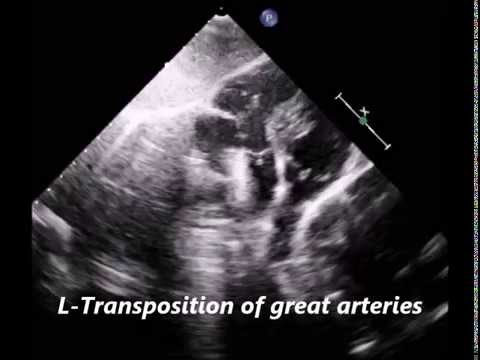

Triple inversion in congenital heart disease